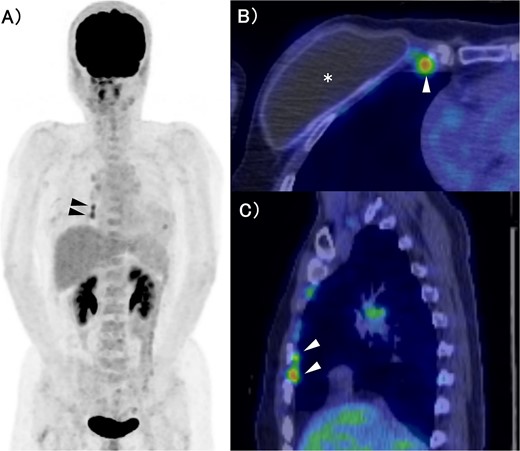

The patient was a 53-year-old woman who had undergone right total mastectomy, axillary lymph node dissection, and implant-based reconstruction for right breast cancer 19 years prior to presentation. The histological findings were TisN0M0, ductal carcinoma in situ (DCIS), and immunostaining was ER positive, PgR positive, and HER2 positive. Hormone therapy (luteinizing hormone-releasing hormone agonist for 2 years and tamoxifen for 6 years) was commenced postoperatively. Fluorodeoxyglucose (FDG) positron emission tomography/computed tomography as health check up performed at another hospital 1 year prior to presentation revealed enlargement of the right IMs, suggesting recurrence of breast cancer (Fig. 1). There were no particular findings to suspect capsular contracture and the Baker Grade was assumed to be grade I with no calcification and aesthetic status was quite good. IM biopsy was performed using VATS to preserve the artificial breast implant. The operative procedure was as follows; a total of three incisions were made in the second, third, and fourth intercostal spaces in the left lateral recumbent position (Fig. 2). The internal mammary artery and vein can be seen thorough the parietal pleura (Fig. 3A). The parietal pleura were dissected along the internal mammary artery and vein (Fig. 3B). En bloc resection of IM from the chest wall was performed (Fig. 3C). The enlarged IM was widely resected (Fig. 3D). The operative time and blood loss were 157 min and 20 ml, respectively. The postoperative course was favourable. The chest drainage tube was removed on postoperative day (POD) 1, and the patient was discharged at POD 3. IM revealed reactive enlargement caused by inflammation.

FDG-PET/CT. (A) MIP section. (B) Horizontal section. (C) Sagittal section. The asterisk and arrow indicate the artificial breast implant and IMs, respectively. FDG accumulation was observed in the IMs. FDG: Fluorodeoxyglucose, PET: Positron Emission Tomography, CT: Computed Tomography, MIP: Maximum Intensity Projection, IM: Internal Mammary lymph node.